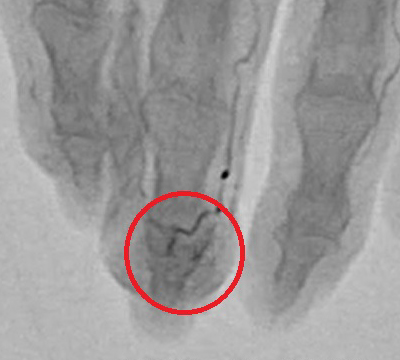

超音波検査や血管造影検査などでは、血管がモヤモヤと集まって見えることから、「モヤモヤ血管」と呼ばれています。

モヤモヤ血管画像 提供元:Okuno Clinic. 奥野 祐次医師